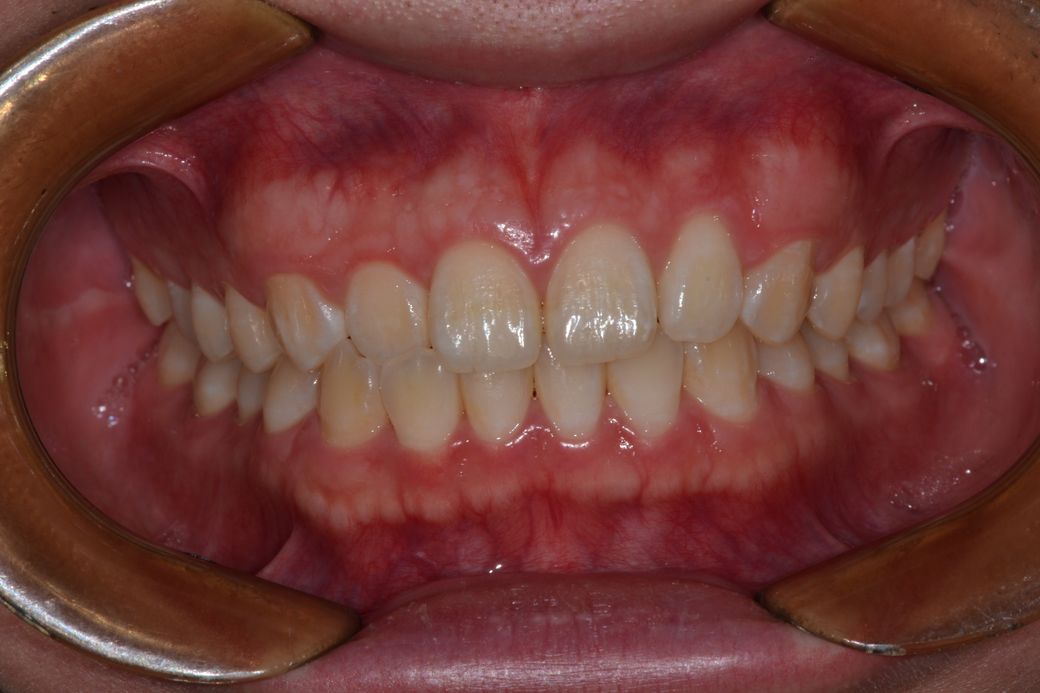

• 4번 째 사진

현재 치열 상태에서는 교정을 쉽게 권하지 않으며 치열이 양호한 편입니다. 다만 본인이 불편한 부위가 있다면 치과 방문 후 이에 대한 검사를 해보는 것이 필요합니다. 치열 자체는 정상적입니다.

-사진때문에 그런지는 몰라도 교합시 치아가 약간 깊게 물리는거 같습니다.